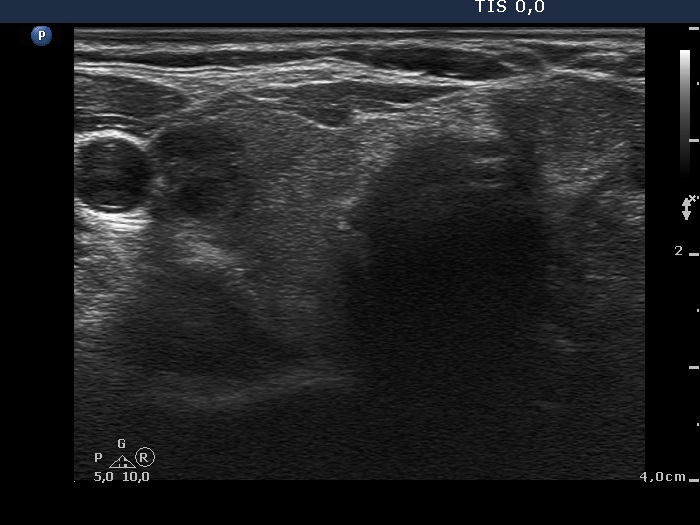

Ultrasonography. The thyroid was echonormal and had a small hypoechogenic lesion in the ventrolateral part of the right lobe. There was a hyperechogenic nodule having coarse calcification in the isthmus while the left lobe also had discrete lesions.